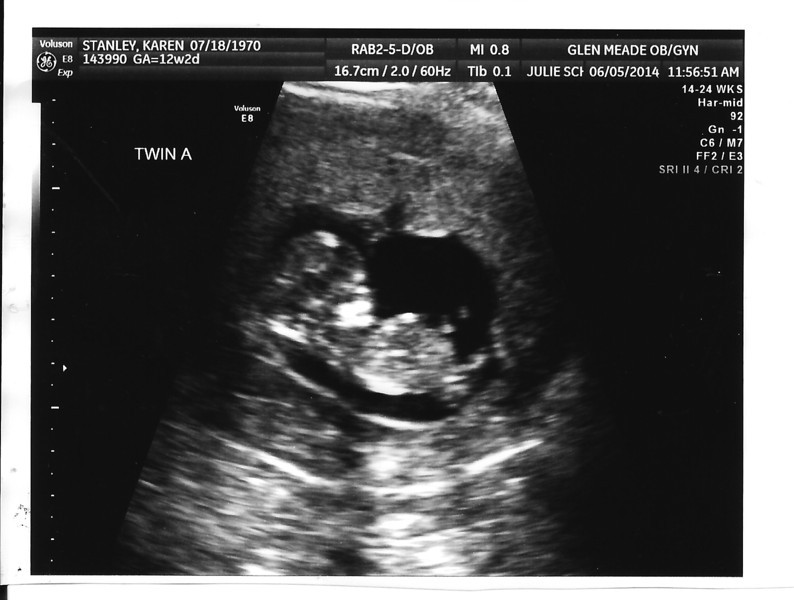

I don't see any nubs. Congrats on the twins

I don't see nubs either but congrats!

I don't see any nub either but for a just for fun guess I say twin a girl twin b boy ! Sent from my iPad using Tapatalk